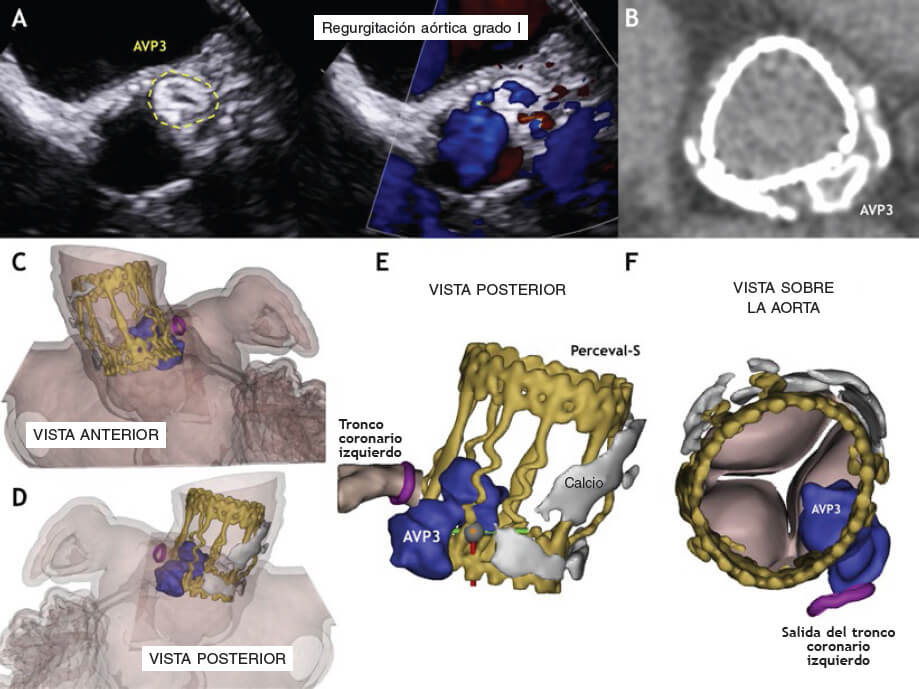

La intervención se llevó a cabo utilizando un dispositivo Amplatzer Vascular Plug III de 10 x 5 mm (AVP3) (St. Jude Medical, Estados Unidos) (figura 1C-G, vídeo 3 y vídeo 4 del material adicional). Se colocó un stent farmacoactivo (SFA) no implantado en el tronco coronario izquierdo (TCI) para evitar posibles oclusiones. Después de la liberación, el TCI se mantuvo permeable y se procedió a recuperar el stent (figura 1D, vídeo 5 del material adicional). La ETE tras procedimiento confirmó el descenso significativo de la FPV (figura 1E,F). La tomografía computarizada multicorte (TCMC) que se realizó 6 meses después confirmó la relación anatómica entre el dispositivo AVP3, los velos de la prótesis Perceval y el TCI. Basándose en esta TCMD, se realizó un modelo en 3D que confirmó la ausencia de interferencias con los velos de la prótesis o el TCI. La ETE confirmó la presencia de TCI permeable y FPV leve (figura 2, vídeos 6-8 del material adicional).

Figura 2.

Se trata del primer caso de cierre percutáneo de una FPV en una prótesis Perceval. Cuando la FPV es adyacente al ostium coronario, es recomendable proteger con un stent no implantado y así evitar el cierre abrupto del vaso. Los modelos tridimensionales se emplean con anatomías complejas para entender mejor la relación existente entre el dispositivo y las estructuras colindantes.